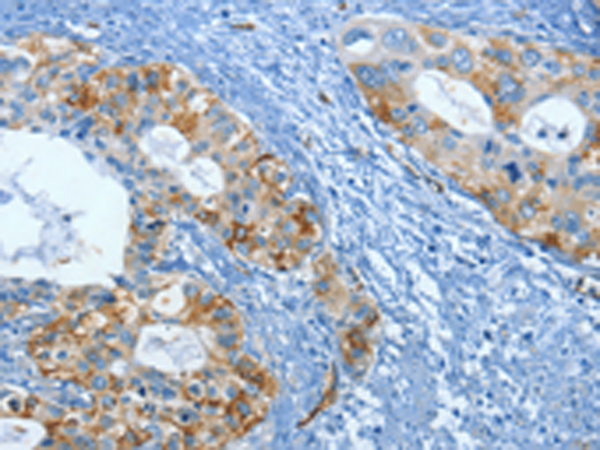

分类: 科研抗体货号: P00199别名: DTL; BAFF; BLYS; CD257; TALL1; THANK; ZTNF4; TALL-1; TNFSF20应用: WB,IHC反应种属: Human